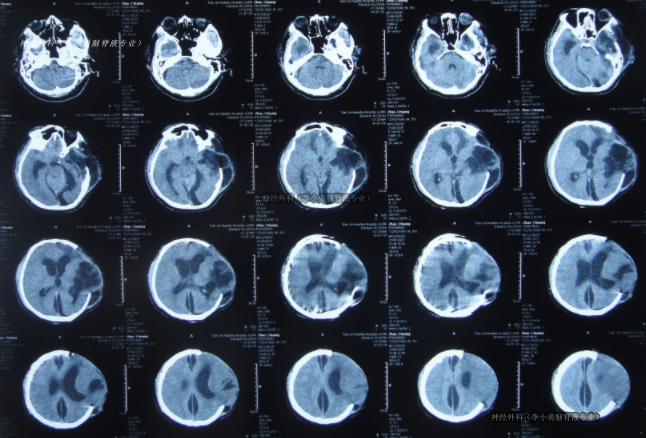

开颅术后第4天放置脑室外引流,第7天因担心感染拔除。患者虽逐渐清醒,但术后第29天转至第3家康复医院后,出现呕吐、问话不答、右侧肢体瘫痪。复查CT示脑室扩张、脑膨出——脑积水已明确形成。

此后,该院两次尝试腰大池引流,均因反复堵管失败。拔管后患者状态再次恶化。开颅术后近2个月,患者从天津转至北京李小勇脑脊液专业。